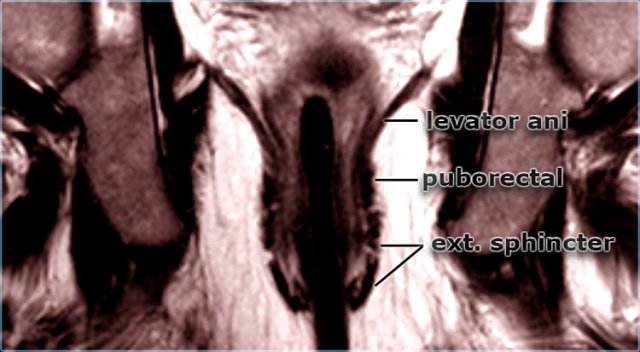

Coronal T2W-image Coronal T2W-image

On axial and coronal MR-images the different layers of the anal sphincter and the surrounding structures can be displayed perfectly.